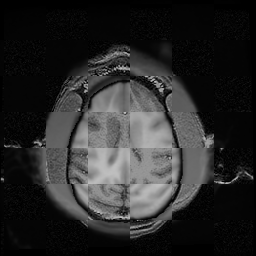

For each of the 10 subjects, we show checkerboard slices in each direction (1) before registration, first row; (2) after rigid->scaleversor->affine registration, second row; and (3) after BSpline registration, third row.

Calvin